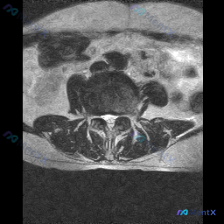

这是一张腰椎MRI T2加权轴位图像,结合解剖结构判断为腰椎下段椎间盘层面,我们先来看具体的影像表现:

- 椎体与椎管结构:中央为椎体截面,后方椎管内蛛网膜下腔高信号清晰,马尾神经根形态、分布正常;椎体边缘信号均匀,未见明确Modic改变,后方附件结构连续,无骨质破坏。

- 椎间盘表现:椎间盘信号略低于正常髓核,提示轻度退变(水分减少),但椎间盘后缘无局限性突出压迫硬膜囊,也未见明确高信号裂隙(HIZ),纤维环完整性尚可。

- 关节与周围组织:双侧关节突关节间隙清晰,周围软组织无肿胀;两侧椎旁肌形态对称,无萎缩或脂肪浸润。

- 神经通路情况:椎管形态大致正常,无明显狭窄;硬膜囊形态饱满,双侧侧隐窝和神经根通道空间充足,没有骨赘或黄韧带肥厚压迫神经根。

影像学综合印象:该层面未见明确腰椎间盘突出,椎管、硬膜囊及神经根无受压,仅提示轻度椎间盘退行性改变。同时要注意,本病例仅提供这单一层面图像,无法评估全脊柱情况。